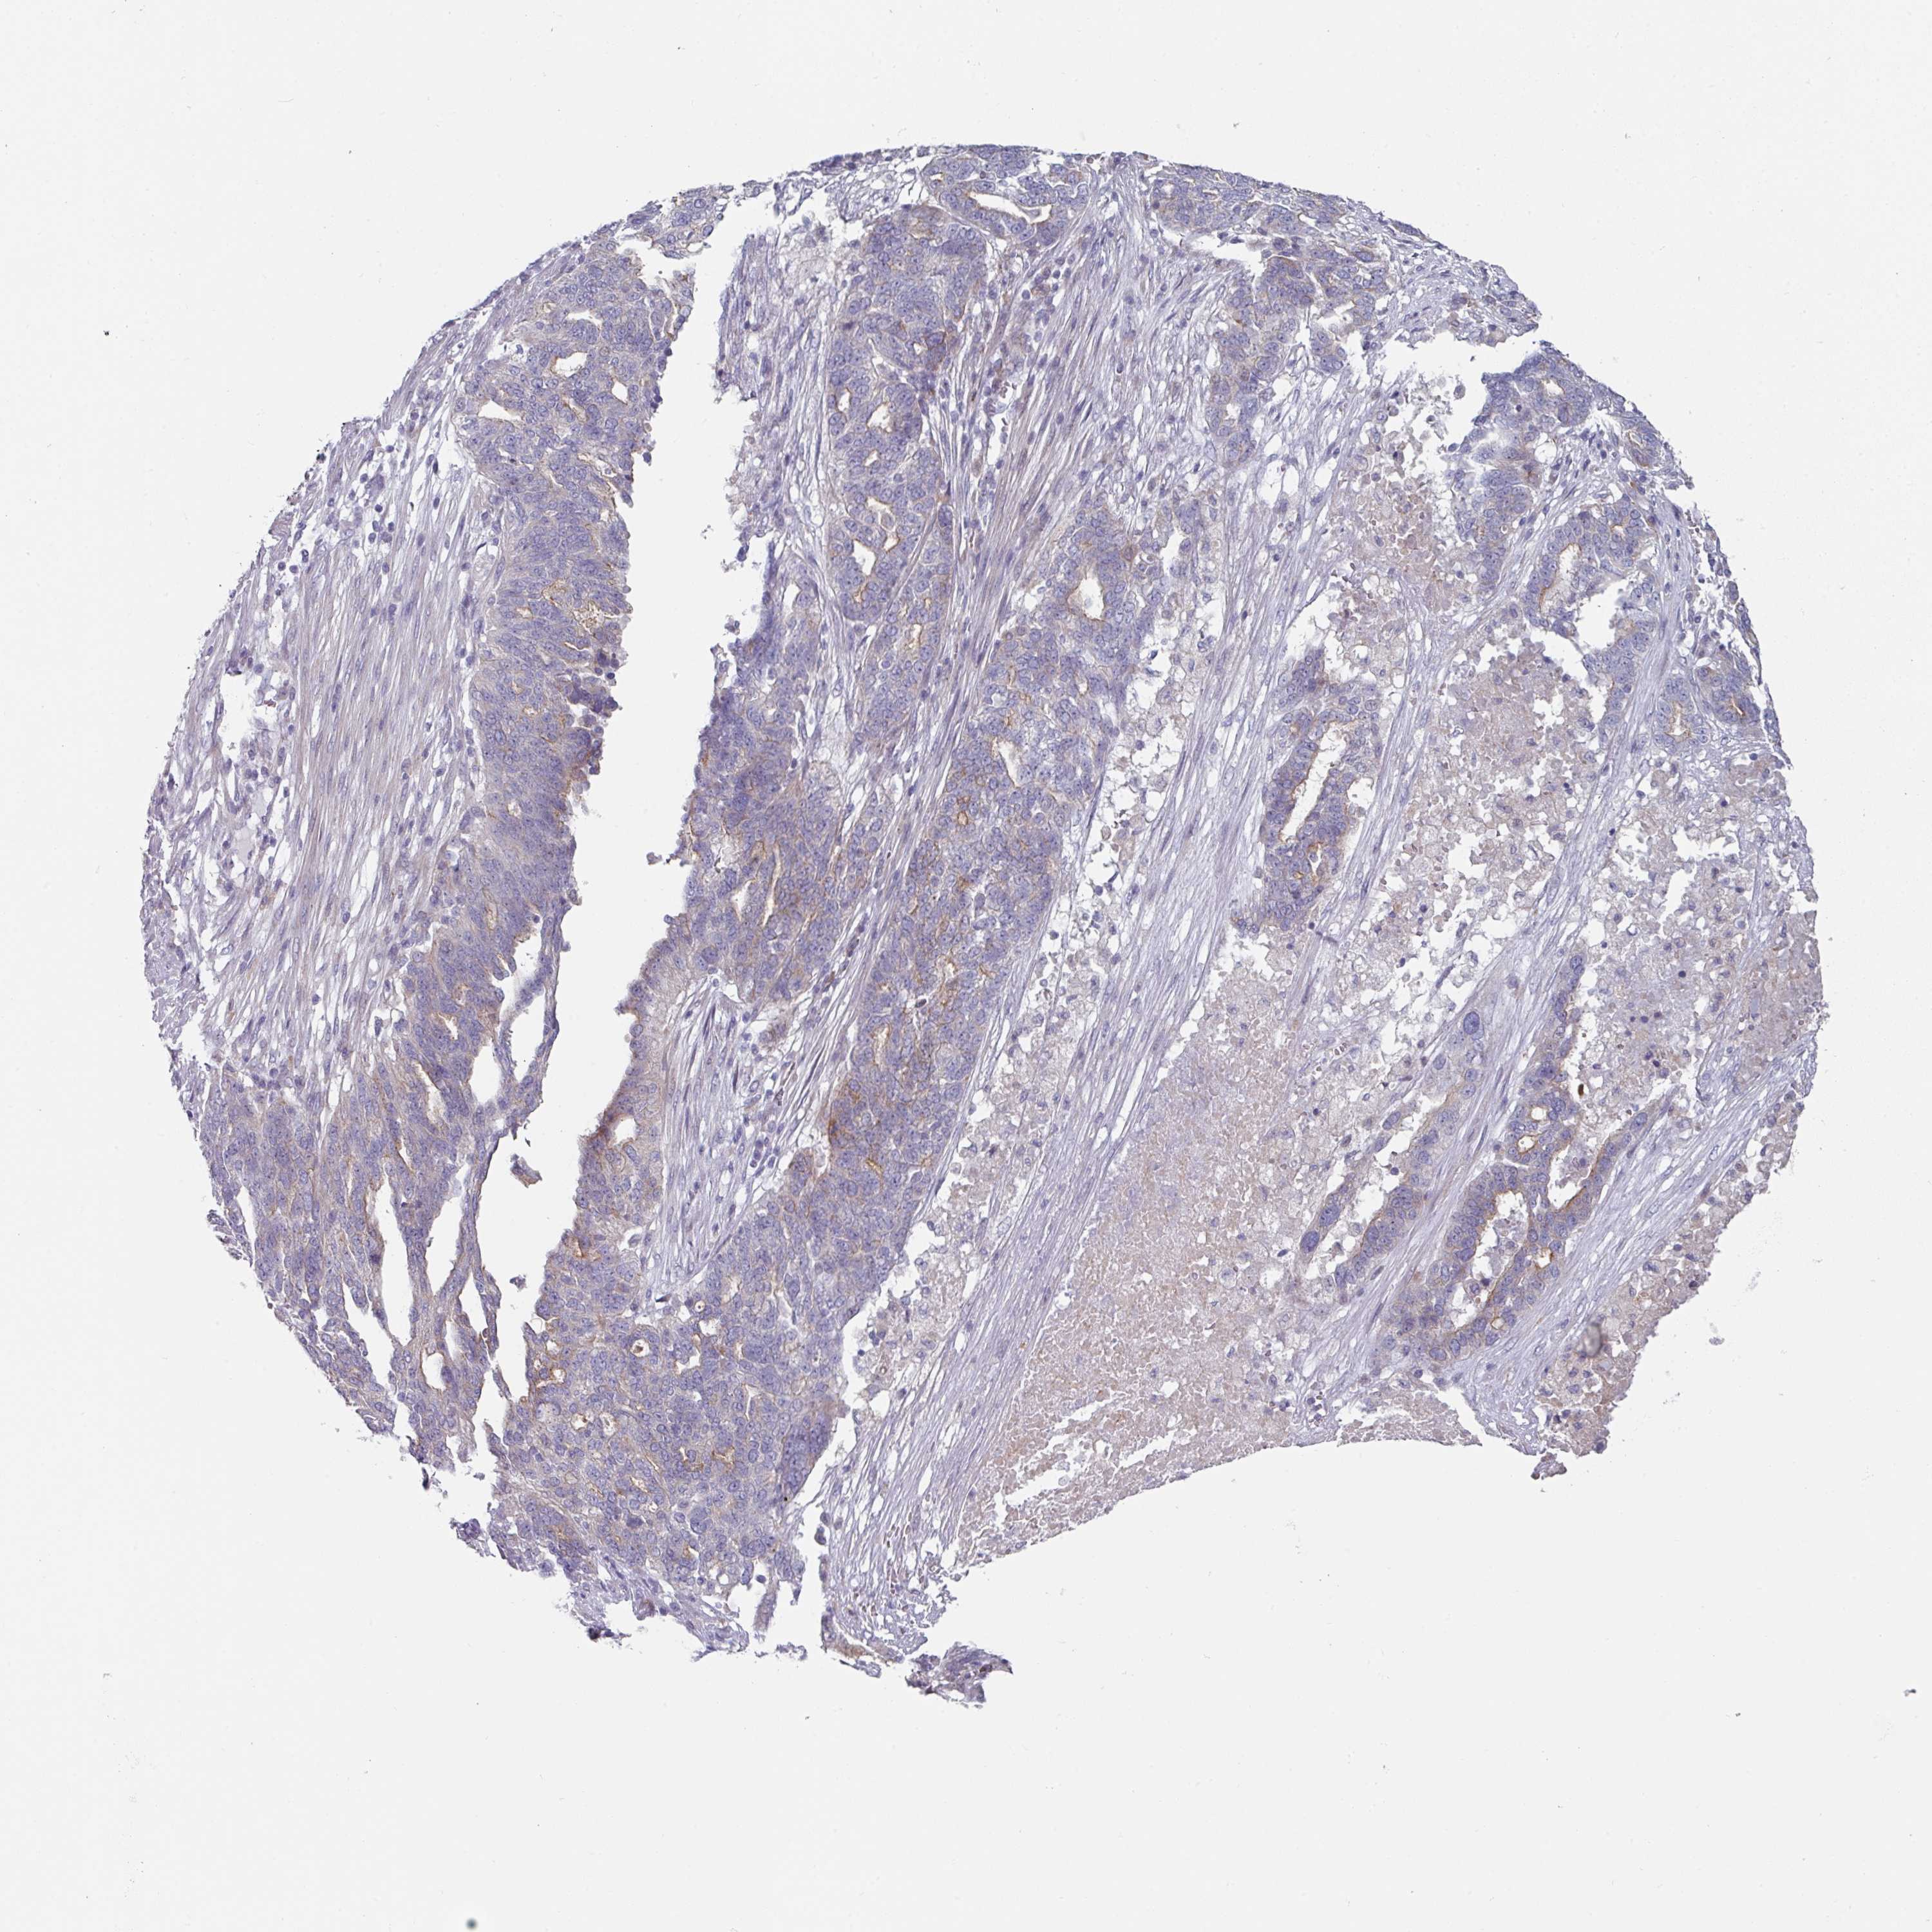

OVARIAN CANCER - Protein expressioni

A mouse-over function shows sample information and annotation data. Click on an image to view it in a full screen mode. Samples can be filtered based on level of antibody staining by selecting one or several of the following categories: high, medium, low and not detected. The assay and annotation is described here.

Note that samples used for immunohistochemistry by the Human Protein Atlas do not correspond to samples in the TCGA dataset.

Antibody stainingi

Antibody staining in the annotated cell types in the current human tissue is reported as not detected, low, medium, or high, based on conventional immunohistochemistry profiling in selected tissues. This score is based on the combination of the staining intensity and fraction of stained cells.

Each image is clickable and will lead to virtual microscopy that enables deeper exploration of all samples and also displays staining intensity scores, fraction scores and subcellular localization as well as patient and tissue information for each sample.

Antibody HPA052606

Antibody HPA077139

Staining

High

Medium

Low

Not detected

Intensity

Strong

Moderate

Weak

Negative

Quantity

>75%

75%-25%

<25%

None

Location

Nuclear

Cytoplasmic/membranous

Cytoplasmic/membranous,nuclear

Cystadenocarcinoma, serous, NOS

Carcinoma, endometroid

Cystadenocarcinoma, mucinous, NOS

Carcinoma, NOS